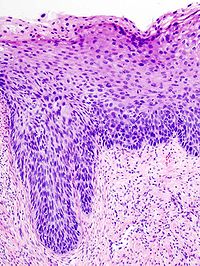

Neoplastik değişiklikler skuamokolumnar bileşkeden (junction) başlar. Serviks kanseri gelişmesinde serviks epitelinde birbiri ardısıra gelen değişiklikler olur, bu da serviks kanserinin erken tanısında önem taşır.

Bu değişiklikler sırasıyla:

1. Normal endoservikal kolumnar epitel

2. Skuamöz metaplazi

3. Hafif-orta-ağır displazi

4. Karsinoma in situ

5. Mikroinvazif karsinom

6. Belirgin invazif karsinom, şeklindedir.

Premalign lezyonların evrelendirilmesi

Preinvaziv servikal hastalık kavramı, 1947 senesinde invaziv kanser görünümüne sahip ancak epitelle sınırlanan epitelial değişiklikler tanımlandığında ortaya atılmıştır. Displazi ve CIS’ın (Karsinoma in situ) sürekli bir olayın farklı basamaklarını teşkil ettiğini düşünen Richart, 1967 yılında servikal intraepitelial neoplazi (CIN I, II, III) terimini tanımlamıştır. Sonraki çalışmalar bu lezyonların tedavi edilmemeleri halinde servikal kansere yol açabileceğini gösterdi. Şimdi ise tedavi edilmediği zaman erken CIN lezyonlarının çoğunun eş zamanlı olarak gerilediği bilinmektedir. Günümüzde anormal lezyonların gelişiminde premalign displastik değişikliklerin değerlendirilmesi için CIN sistemi kullanılmaktadır.

Servikal intraephitelial neoplazi (CIN):

* CIN I Hafif displazi (atipik hücreler epitelin alt 1/3’ünde sınırlı)

* CIN II Orta displazi (atipik hücreler epitelin alttan 2/3’lük kısmında ise)

* CIN III Ağır displazi (epitelin tamamına yakını tutulmuş ise)

* CIS Karsinoma in situ (epitelin tamamı tutulmuşsa)

Not I: CIN I düşük evreli skuamöz intraepitelyal lezyon; CIN II/III yüksek evreli skuamöz intraepitelyal lezyon olarak da isimlendirilir.

Not II: Bütün lezyonlarda bazal membran sağlamdır.

İnvaziv servikal kanserler genellikle uzun bir preinvaziv hastalık evresini izlerler. Mikroskopik olarak, invaziv karsinomlara ilerlemeden önce hücresel atipiden, değişen derecelerde servikal intraepitelyal neoplazilere (CIN) ilerleyen prekürsor lezyonlar spektrumu ile karakterizedir. CIN I lezyonlarının büyük çoğunluğunun geçici olduğu; kısa dönemlerde normale gerilediği veya yüksek derecelere ilerlemediği iyi bilinmektedir. Diğer taraftan, yüksek dereceli (CIN II, III)’ler, her ne kadar bu tür lezyonların da bir kısmı gerilese de, yüksek oranda invaziv kansere ilerleme olasılığı taşır. Servikal öncü lezyonların invaziv kansere ilerlemesinin ortalama 10 ila 20 yıl kadar uzun bir zaman aldığı bilinmektedir.